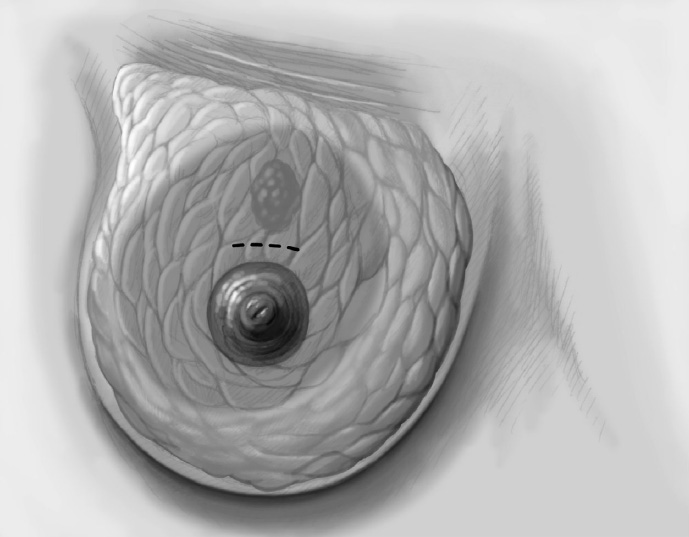

The basic decision on whether to use a complex oncoplastic technique is made when the skin is marked preoperatively, with the patient standing or sitting upright. Many surgeons successfully combine the B-plasty incision with periareolar de-epithelialization and excision of a straight or curved ellipse of peripheral skin (Chapter 1.3). When marking the periareolar deepithelialization pattern, an eccentric incision may be necessary to adjust the repositioning of the nipple–areola complex to the anticipated volume displacement.

The periareolar skin is de-epithelialized. Here, too, there are various options. A strip of the most superficial skin layer can be excised with dissecting scissors applied flat or with a scalpel. It is important not to leave behind any surface containing squamous epithelium, but on the other hand the dermis and the important vascular layer beneath it must not be injured. The purpose of periareolar de-epithelialization is to recenter the nipple–areola complex and also to tailor excess skin to the new breast shape following extensive tumor resection.

Segmental excision of the area containing the tumor with resection margins as wide as possible to meet oncological criteria. Oncoplastic techniques should be used to achieve maximal oncological safety and avoid subsequent further resection.

The nipple is repositioned at the most cranial point of the measured periareolar de-epithelialization area. If nipple repositioning over a long distance is necessary, a domelike extension in a cranial direction can be de-epithelialized beyond the purely periareolar de-epithelialization area (LeJour technique).